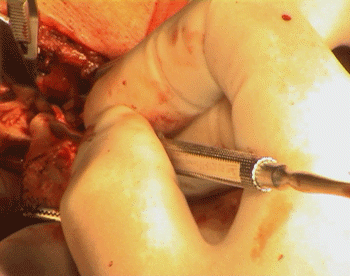

The patient under G.A with nasal intubation, in case he needs high dissection, were performed. Incision was made to expose the distal 3 cm of the CCA and the ICA until the upper edge of the stint was felt. The ECA was dissected and the superior thyroid artery. All was done with the BP of the patient kept at 170/100 mm Hg. and continuous cover of the patient with 500 units of heparin/hour. An-Argyle-like tube was prepared in case, but when it was found that, the back flow of the ICA was weak, it was decided that, no need for such shunting.  For technical details of the operative details, you can refer to this article.

The atheroma was completely occluding the soft construct of the stint, with minimal clot inside the very shallow space inside the compressed stint. After removal of the stint, it regained its cylindrical configuration, as seen in the lower pictures.

Water-tight closure of the vascular wall with 6 zero nylon and the carotid bulb and major branches were checked for the flow and presence of bleeding points. Meticulous heamostasis and ready-vac drain  No 8 left in the wound.

Exposure of the atheroma in the CCA. Sharp cut of the atheroma at the CCA.

The lower edge of the stent is seen inside the atheroma. The stent and atheroma completely occluding the ICA.

Fine dissection is going on. The atheroma is removed from the superior thyroid artery.

The atheroma is dissected from th ECA. Cutting the atheroma from the ECA.

Further cleaning of the debris after removal of the mess. The carotid bifurcation after repair with nylon 6 zero.

Stages of atheroma with stint removal. Notice that the atheroma was extending far to the ECA and even the STA!